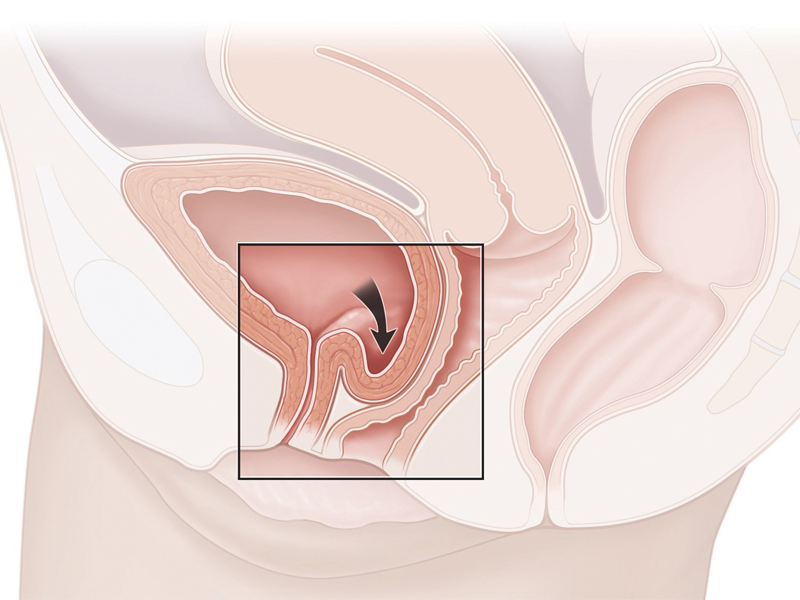

Sa bàng quang độ 3

Tiến sĩ bác sĩ Lê Phúc Liên, Trưởng Đơn vị Niệu nữ, Trung tâm Tiết niệu – Thận học – Nam khoa, cho biết người bệnh đến khám vì tình trạng tiểu không kiểm soát khi gắng sức (ho, hắt hơi, cười lớn, mang vác nặng…). Mức độ són tiểu ở mức trung bình, phải thay quần lót 3-4 lần mỗi ngày. Tuy nhiên, khi thăm khám, bác sĩ phát hiện thêm người bệnh bị sa bàng quang độ 3. Đây là nguyên nhân khiến tình trạng són tiểu nặng hơn.

Sa bàng quang là tình trạng thay vì ở vị trí đúng trong vùng chậu, cơ quan này tụt xuống âm đạo và sa ra ngoài. Nếu không điều trị sớm, bàng quang có thể sa ra ngoài hoàn toàn (độ 4). Lúc này, khối sa có thể lở loét, nhiễm trùng do cọ xát với quần áo, cơ thể. Ngoài biến chứng són tiểu, người bệnh có nguy cơ bí tiểu, thận ứ nước, suy thận. May mắn, người bệnh khi nhập viện chưa có các biến chứng này.